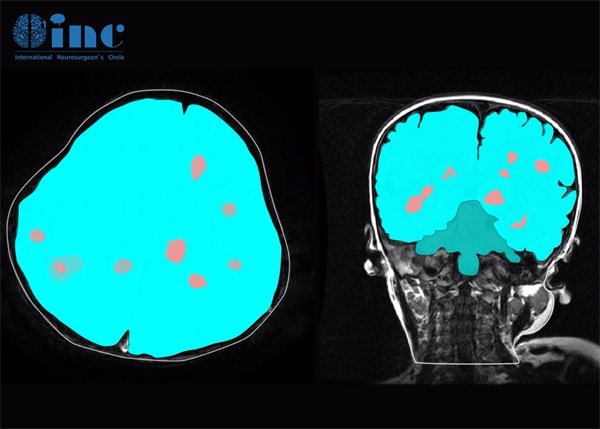

右顶叶海绵状血管瘤怎么治疗怎么发现?常见的发现方法是通过磁共振成像(MRI)或计算机断层扫描(CT)进行筛查。右顶叶海绵状血管瘤的治疗选择通常取决于以下因素:病变的大小、位置、患者的症状表现及总体健康状况。主要治疗方式包括:手术治疗、药物治疗等。右顶叶海绵状血管瘤是脑血管畸形的一种,通常在影像学检查中意外发现。尽管它们通常是良性的,但当它们位于大脑的关键区,如右顶叶时,可能会引发一些神经功能障碍。

常见的发现方法是通过磁共振成像(MRI)或计算机断层扫描(CT)进行筛查。